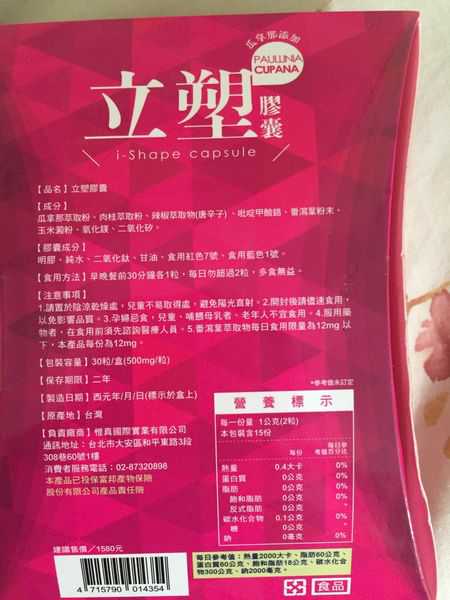

Supercut塑魔纖立塑膠囊的成分有:瓜拿那萃取粉、肉桂萃取粉、辣椒萃取物(唐辛子)、吡啶甲酸鉻、番瀉葉粉末、玉米澱粉、氧化鎂、二氧化矽。

之前上過相關課程,成分表是依照每項成分的多寡來排列順序,排在最前面的就是產品的主要成分!

食用方式:早晚餐前30分鐘各1粒,每日不超過2粒。(多食無益)

番瀉葉萃取物每日食用限量為12mg以下,

番瀉葉萃取物每日食用限量為12mg以下,